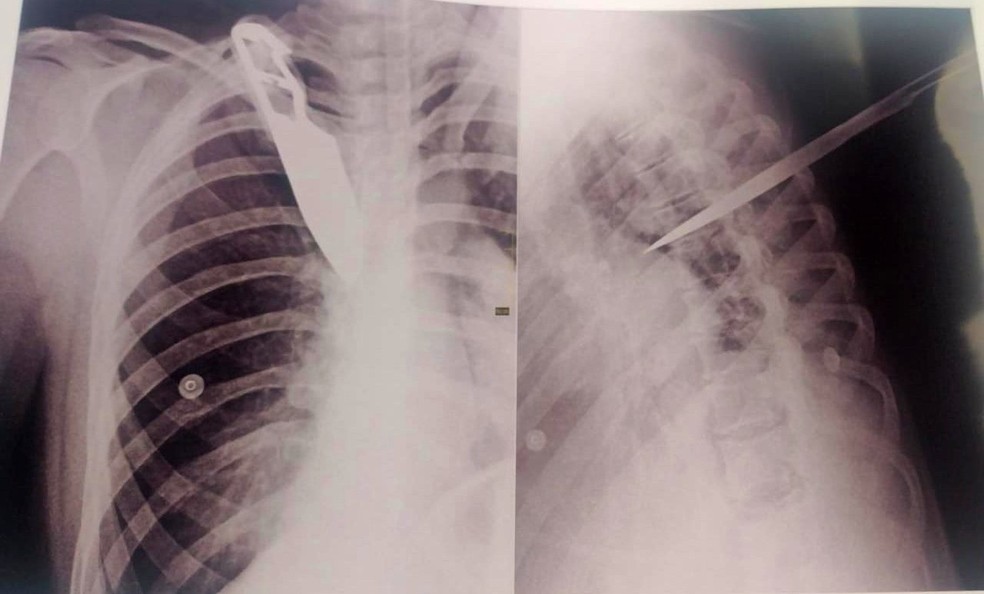

No raio-x foi possível ver a faca cravada no peito da mulher. Foto: Reprodução/Internet

GÁLIA (SP) – A imagem de um raio-x com uma faca cravada nas costas chocou as pessoas que souberam o que aconteceu com uma mulher de 33 anos, em Marília, São Paulo (SP). A vítima, de acordo com a polícia, era a ex-mulher de um detento e a tentativa de homicídio aconteceu durante uma discussão, na terça-feira (28).